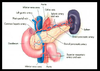

Do the pancreatic exocrine products pass through the ampulla of Vater?

yes

how many anstomoses are there in a transplanted pancreas?

arterial – Donor AO or CA to external iliac artery

venous – Donor PV to external iliac vein

duodenal – exocrine functions to jejunum or bladder